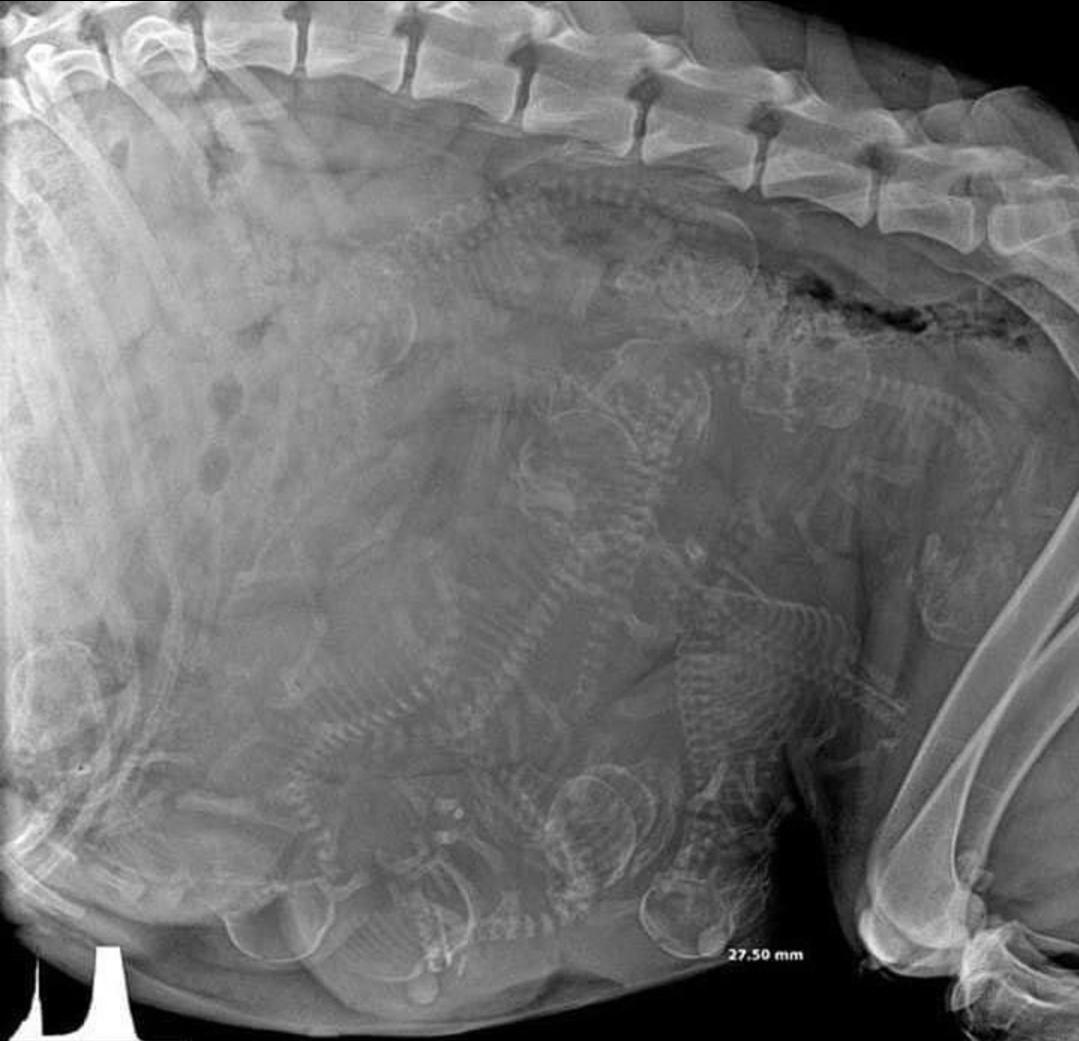

15. 임신한 개의 엑스레이 사진